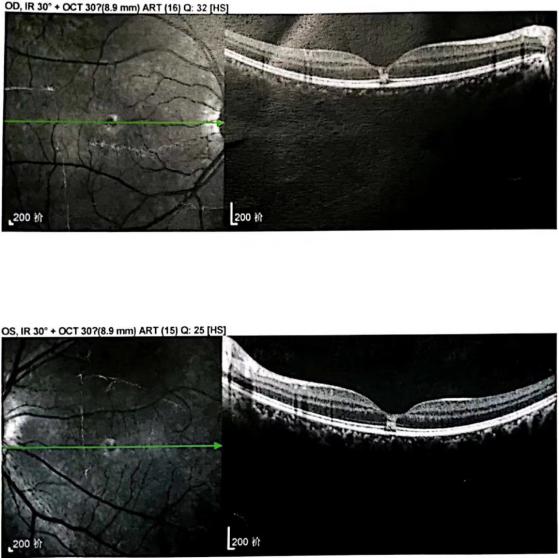

入院后,赵铁英院长给予小秀改善微循环、营养支持治疗用药。“她的视力出现下降,当时矫正视力下降到0.8,经过十多天的治疗,她的暗区变淡了,不特别注意的情况下几乎消失了。通过这段时间她的症状描述,以及我们看到的视网膜各层细胞结构的修复情况,很有信心应该能修复到正常的状态。”赵铁英院长告诉记者。

出院当天,小秀也开心地告诉记者“我现在眼前盘状“暗区”明显缩小了,今天做检查视力也由0.8提升至1.0,赵院长说我可以出院回家了。这和我来之前相比,真的是好太多了,我为赵院长点一个大大的赞。”

(小秀双眼治疗前后视网膜断层扫描图像)